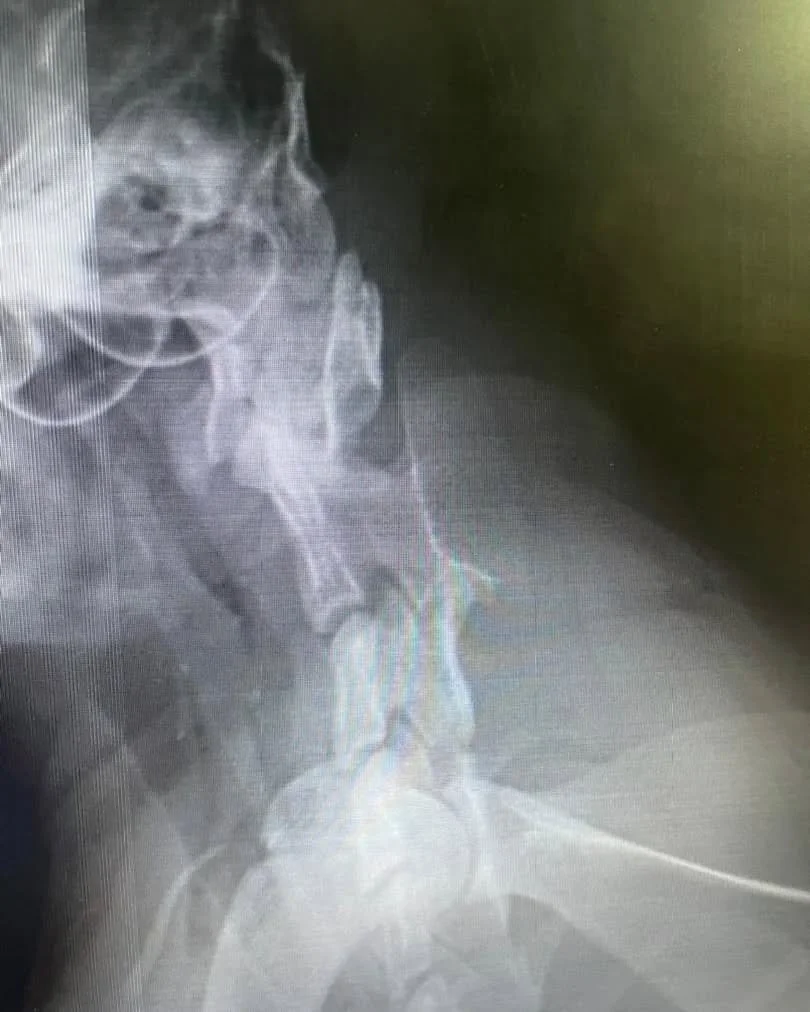

That is how rescuers found her. Firefighters freed her from the box and brought her to us, terrified and weak. But her ordeal was not over. The box’s pressure had badly injured her neck. An examination also revealed that her unborn kittens had not survived, and the infection had already begun poisoning her body.